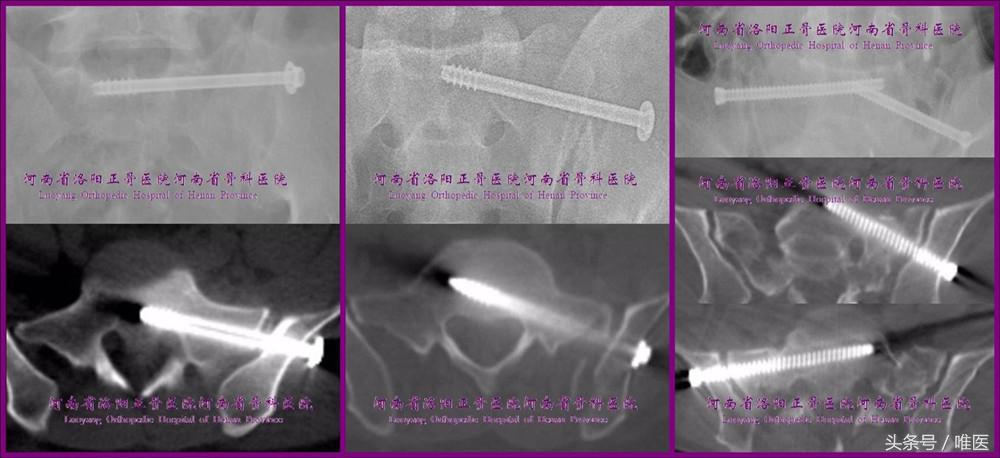

一般情况下,治疗SIJ脱位和骨折脱位的骶髂螺钉多为斜向、部分螺纹,治疗骶骨骨折的骶髂螺钉多为平向、全螺纹;骶1骶髂螺钉可斜向或平向(需根据上骶段的类型及置钉通道的大小而定)置入,骶2骶髂螺钉为平向(如有置入空间);在置入第一枚骶髂螺钉固定SIJ脱位或骶骨骨折后,最好再置入一枚全螺纹骶髂螺钉作为位置螺钉加强固定,从而实现骨盆后环的两点固定(two-pointed stabilization)[10]。(图1)

图1. 骶髂螺钉的类型及“两点固定”示例。